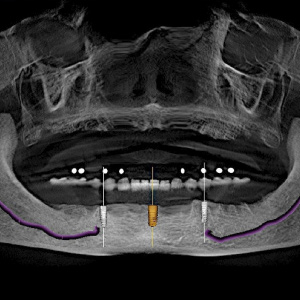

Grand Design: Implant and Full-Arch Solutions for Strength and Stability

Implant therapy has become an integral part of clinical dentistry, with ever-increasing numbers of patients seeking this treatment. However, this good news comes with a significant challenge: patients have increasing expectations for shortened treatment duration - even patients with anatomical deficiencies. You need serious treatment flexibility to create optimal outcomes for all indications. Learn more about advanced system options in this new eBook.

Leveraging AI for Diagnostic Excellence

The newest advancements in diagnostic imaging incorporate assisted intelligence (AI). Software can now help dentists more precisely and accurately identify areas of concern, trace the mandibular nerve, accurately plan dental implants, organize all images into a single template, and much more.